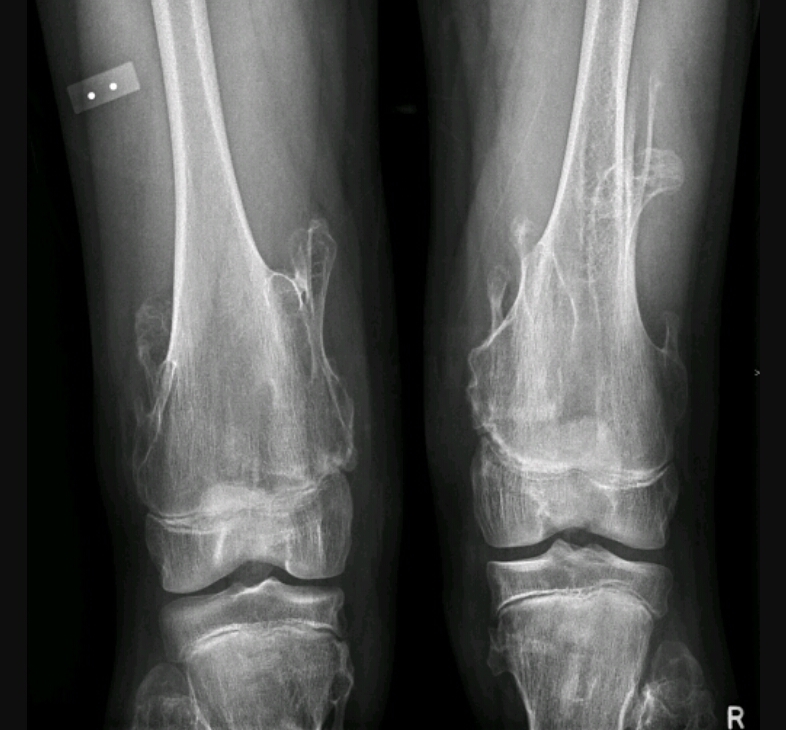

Findings? Diagnosis?

Impaired bone growth, short ulna, bowing of radius, subluxation of the radioulnar joint

Madelung deformity